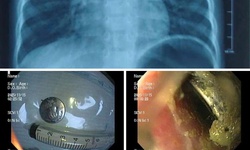

Cứu sống bệnh nhân 41 tuổi bị đột quỵ não, suýt tàn phế vĩnh viễn

Y tế - 26/09/2025 14:13SKĐS - Bệnh nhân nam, 41 tuổi (ở Hải Phòng) bị đột quỵ, may mắn được các bác sĩ tại Bệnh viện Hữu nghị Việt Tiệp cứu sống.